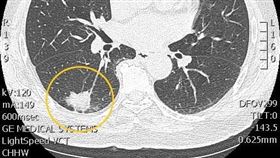

肺癌常見症狀包括咳嗽、血痰、胸悶胸痛、哮喘等,家醫科...

2021/01/04 10:09